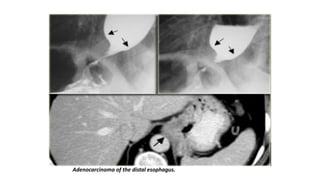

Adenocarcinoma of the distal esophagus.

• A 4 cm segmental narrowing with an irregular margin and shouldering

appearance at the distal half of the esophagus suggests tumoral

infiltration.

• Evidence of prior sternotomy is noted.